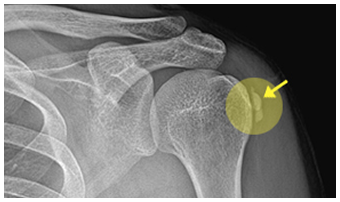

석회제거술이란?

퇴행성 변화로 인해 어깨 힘줄 세포가 괴사하면서 그 조직에 석회질이 침착하게 됩니다.

이로 인해 발생하는 질환인 석회성 건염의 치료 방법 중 하나가

석회성 물질을 제거하고 염증 부위를 절제하는 ‘석회제거술’입니다.

석회화건염

어깨의 회전근개(힘줄) 주변에 석회 물질이 생성되어 극심한 통증을 유발하는 질환을 말합니다.

주로 40~50대 이후 여성에게서 발생하며, 이는 어깨 힘줄의 퇴행성 변화와 관련이 있습니다.

침착된 석회가 치료 후 없어진 모습

before img after img